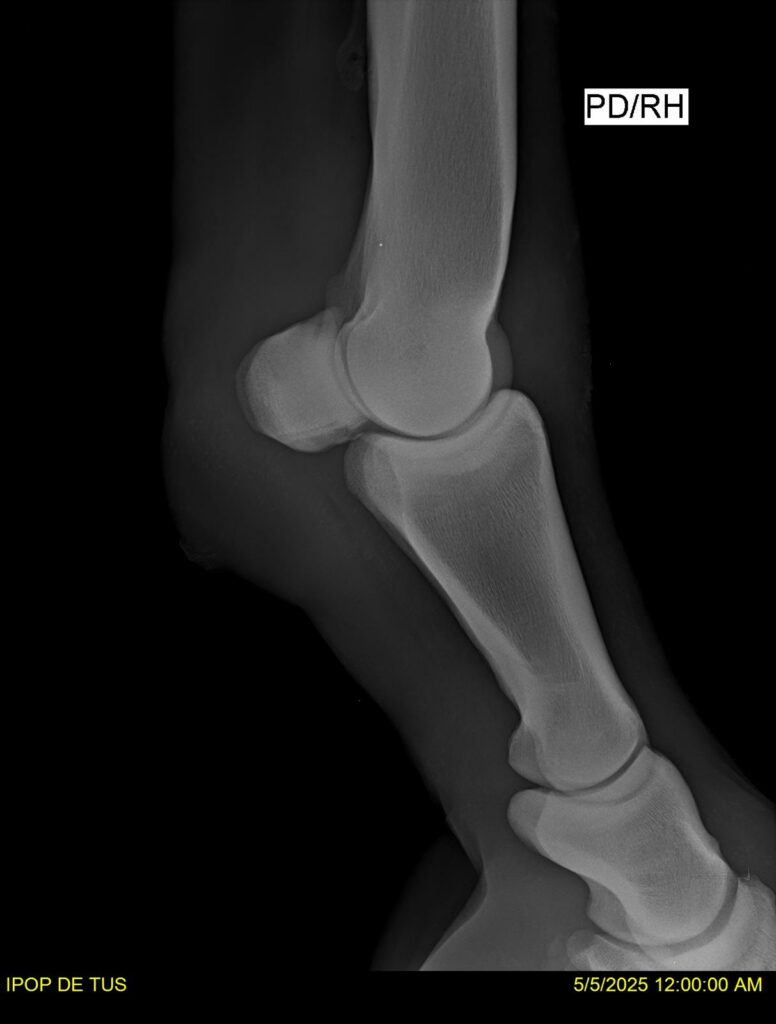

IPOP DE TUS, selle français, hongre, prendra 8 ans en 2026. LIFESTYLE x EROTICBLUS MONTOIS. Sans faute sur 125 et 130. Gentil cheval, respectueux avec des moyens et de la force. Transport OK, maréchalerie OK (pieds nus), santé RAS, Bilan clichés radios + clinique OK.

RADIOS ET CLINIQUE